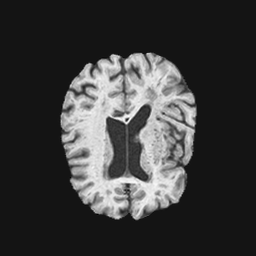

Exp. 2: Fetal brain data is used to test the robustness of our approach under real conditions. Fetuses younger than 30 weeks very often move a lot during examination. Fast MRI sequences allow artifact free acquisition of individual slices but motion between slices corrupts consistent 3D information. Fig. 3 shows that our method is able to accurately predict also under these conditions. For this experiment we use from three orthogonally overlapping stacks of ssFSE slices covering the fetal brain with approximately 20-30 slices each. We are ignoring the stack transformations relative to the scanner and treat each individually. For , 28 clinically approved motion compensated brain reconstructions are resampled into a volume with spacing. A density of 500 unique sampling normals has been chosen via the Fibonacci sphere sampling method with 25 sampling planes evenly spaced between -25 to +25 on the Z-axis. This gives a plane spacing of 2mm, sampling only the middle portion of the fetal brain. Training took approximately 10hrs for 30 epochs. Prediction, i.e., the forward pass through the network, takes approx. 12 ms/slice.

Here we show for Exp. 1, Exp. 2, and Exp. 3 randomly selected examples of images that have been presented to the network (ground truth) compared to an image sampled at the predicted location.

In these experiments, we present a ground truth (GT) image to the network to estimate the respective transformation parameters needed to reorient the slice in its correct world co-ordinates. Using the transformation parameters, we generated a slice from the 3D atlas in the location where the network has predicted that slice should be (denoted as SVRNet).

The slices are compared side-by-side to give a visual representation of “where the slice really is” and “where the network thinks the slice is”.

0..5.2 Exp. 2:

Slices, from a motion corrupted MRI stack, are segmented and cropped. Since there is no ground truth for the queried images, an arbitrary fetal atlas is used for visualization in Fig. 11 and 12.